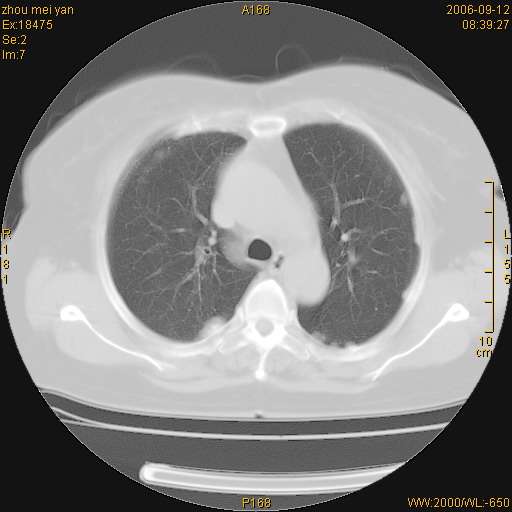

患者、女、55岁。因心率失常住院检查ct发现胸部多发结节。腹部b超肝、胆、胰、脾、肾、子宫附件未见异常。无结核病史,无粉尘接触史。请大家来会诊。谢谢!

病变位于胸膜,多发结节,边界清楚,内见小结节状钙化。其它未见异常。

双侧胸膜多发结节,形态不规则,边缘较清楚,每一个结节中心似乎都有钙化点的特征,与胸膜广基相切。临床无结核病史,无粉尘接触史。

影像表现十分有特点:双侧肋胸膜及膈胸膜广泛散在分布大小在2至6mm左右,较大病灶中心可见钙化。